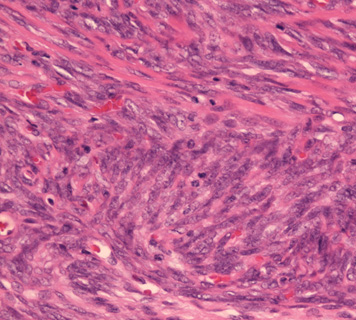

1. biphagic type; 古典的なタイプでさまざまな割合で明らかな上皮成分と紡錘細胞が混在する。

biphasic type, monophasic typeは同じくらいの頻度で出現する。後者では免疫染色で上皮様分化をしめすこと, 特徴的な遺伝子異常を検出することが診断に必要となる。理論的にはmonophagic epithelial typeもあるが形態のみで診断は不可能。わずかな線維肉腫様成分をさがすことが診断にむすびつき, cytogenetic dataにより確診にいたる。